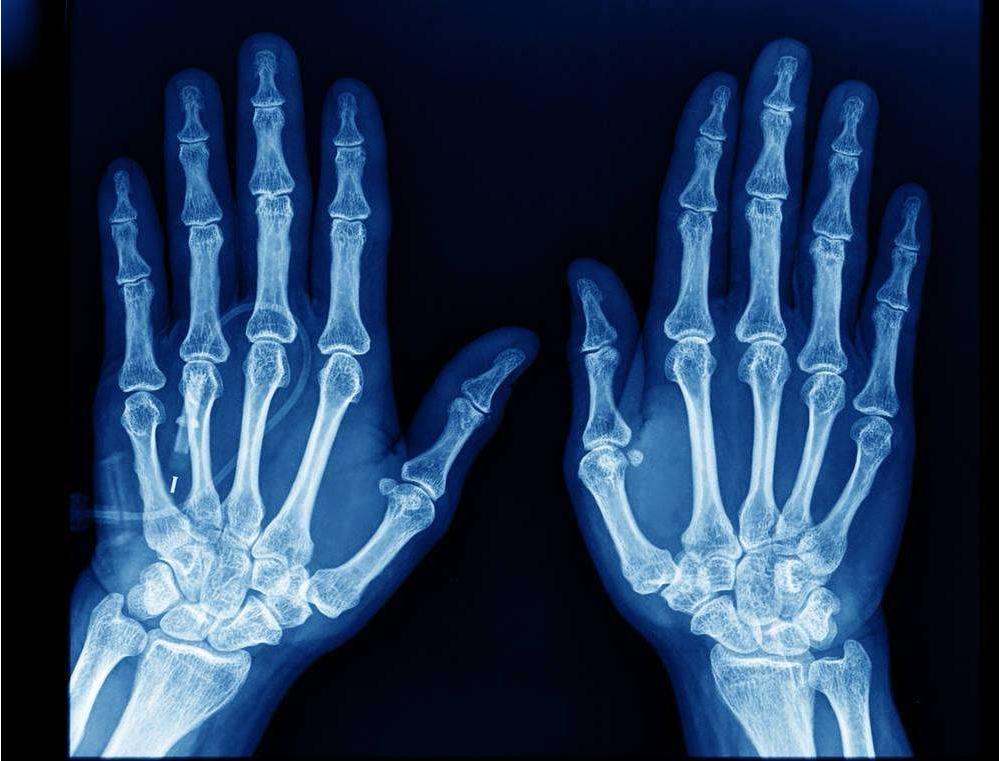

1.3.2 X 射线成像

- 应用场景:医学诊断(骨折、肺部检查)、安检(行李扫描);

- 技术特点:X 射线穿透不同密度物质的能力不同,成像突出边缘和轮廓。